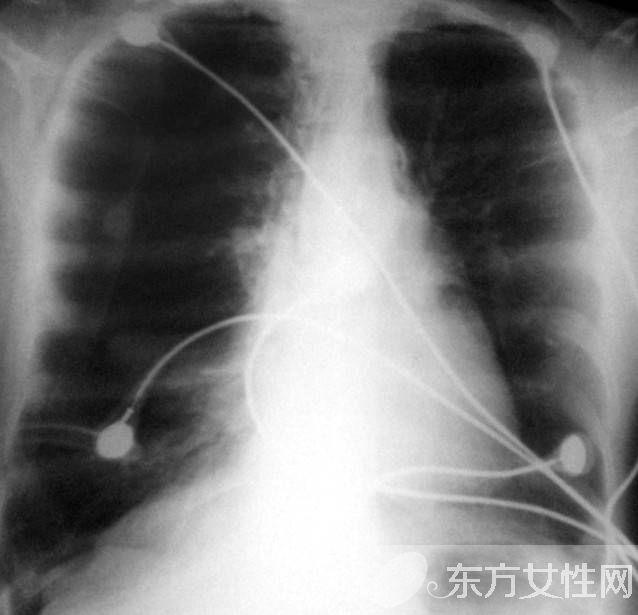

发病缓慢,多有慢性咳嗽、咳痰史。早期症状不明显,或在劳累时感觉呼吸困难,随着病情发展,呼吸困难逐渐加重,以致难以胜任原来的工作。慢支在并发阻塞性肺气肿时,在原有的咳嗽、咳痰等症状的基础上出现逐渐加重的呼吸困难。当继发感染时,出现胸闷、气急,发绀,头痛,嗜睡,神志恍惚等呼吸衰竭症状。肺气肿加重时出现桶状胸,呼吸运动减弱,呼气延长,语颤音减弱或消失,叩诊呈过清音,心浊音界缩小或消失,肝浊音界下降,心音遥远,呼吸音减弱,肺部有湿啰音。部分患者发生并发症:自发性气胸;肺部急性感染;慢性肺源性心脏病。

轻度肺气肿体征多无异常。肺气肿加重时胸廓前后径增大,外观呈桶状,脊柱后凸,肩和锁骨上抬,肋间隙饱满,肋骨和锁骨活动减弱。语颤减弱,叩诊呈过清音,心浊音界缩小或消失,肝浊音界下降。呼吸音及语颤均减弱,呼气延长。有时肺底可闻及干湿啰音,心音遥远,肺动脉第二心音亢进。重度肺气肿患者,即使在静息时,也会出现呼吸浅快,几乎听不到呼吸音。可出现发绀,合并肺心病右心衰竭时可出现颈静脉怒张、腹水、肝大,凹陷性水肿等体征。